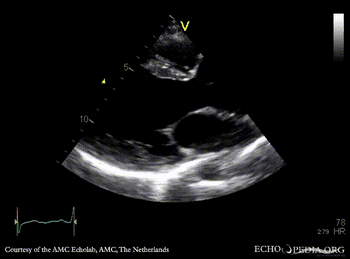

E00442.gif E00443.gif

PLAX: dilated left ventricle and ascending aorta in patient with Marfan syndrome PLAX: dilated ascending aorta